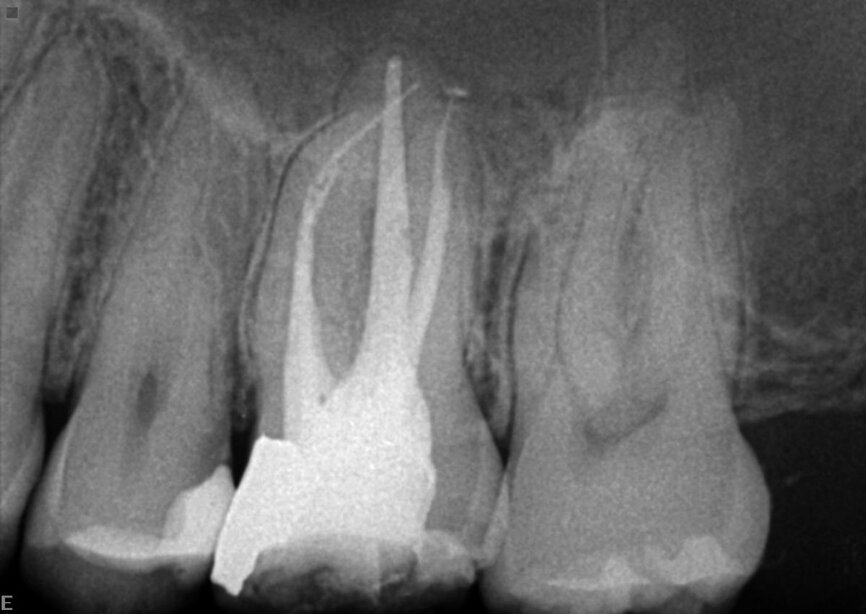

The patient was referred for a dull pain affecting a maxillary molar. On the preoperative radiograph, we could see a diversity of obturation materials, including single cones, resin cement and silver cones, with some of them already fragmented and one piece protruding from the root. Looking closely at the sinus and the sinus membrane, we could see that the membrane had been perforated by the inflammatory/infection process, which had led to sinus infection (Fig. 15).

Under the operating microscope and using ultrasonic and K3XF rotary files (Kerr Dental), I managed to clear the root system of all the previous obturation materials, and placed a dry cotton pellet and temporary cement, as the patient had become tired during this long appointment (Fig. 16). Figure 17 shows some minor debris of silver cones that had passed beyond the mesial apex and using the MacroCannula of the EndoVac, I managed to retrieve one small piece of the silver cone and to complete the chemical cleaning of the root canal system.

Figure 18 shows the immediate postoperative situation, focusing on the obturation of the mesial canals, and a slight improvement of the membrane and the sinus is evident. Figure 19 shows the three-month follow-up with an almost complete closure of the membrane and the bone of the sinus floor.